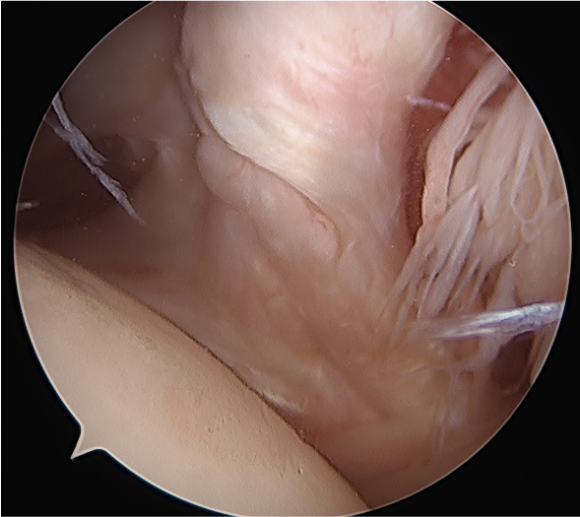

2. Retracted tendon tear

- tag and release biceps tendon

- lateral traction sutures in subscapularis

- extensive tendon release with cautery and recreate rotator interval

- repair as above

Lateral traction sutures placed in subscapularis, then cautery used to remove scar tissue and recreate rotator interval